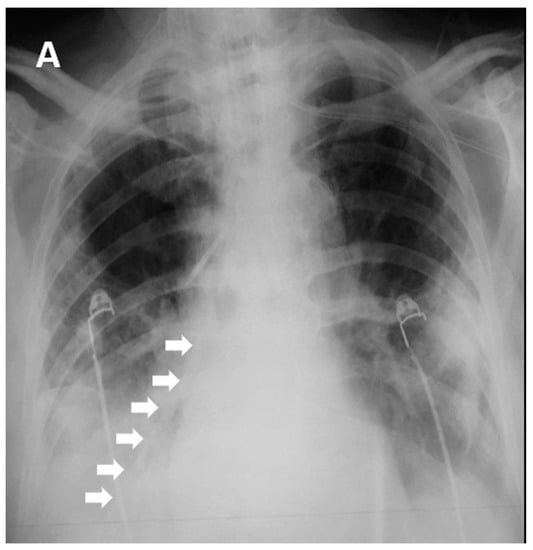

Two hundred and seventy-seven patients with COVID-19 ARDS were admitted in the ICU, and one was excluded from the analysis as he had undergone bariatric surgery 10 years previously (Figure 2, Table 1). All 282 patients, apart from three, had a NGT placed immediately after ICU admission. Those three patients were proned immediately after admission without a NGT, which was placed after they returned to the supine position. After the first six COVID-19 ARDS patients were admitted to the ICU, we faced one unfortunate NGT misplacement in a patient who turned to the supine position after he had been proned for sixteen hours. A chest X-ray was delayed, and enteral feeding was initiated after a “palpation” positive test. Eight hours later the patient became severely hypoxemic with increased secretions. Chest X-ray revealed that the NGT had been positioned in the right lower lung lobe (Figure 1). After that we decided to adopt a protocol of ultrasonographic confirmation of correct NGT position.

Ultrasonographic evaluation of NGT position was performed in 276 patients, and confirmation of correct NGT placement was feasible in 246/276 (89.13%) patients. In 189/246 (76.8%) the tube could be visualized in the stomach (Figure 3), in 172/246 (69.9%) the ultrasonographic whoosh test was evident (Figure 4, Videos S1 and S2), while in 164/246 (66.7%) both tests confirmed correct NGT placement. All the patients had additional confirmation with palpation of a “flash” of air in the epigastrium instilled through the NGT. In the patients in whom the NGT could not be visualized and an ultrasonographic whoosh test was negative, a chest X-ray was performed. In all patients the NGT was located in the stomach.

Five hundred ninety ultrasonographic evaluations, in total including an initial evaluation and re-evaluations, were performed during the study period. Four hundred sixty-two (78.3%) confirmations of correct NGT placement could be evaluated (Table 1, Figure 2). In the 128 cases (21.7%) where the NGT could not be visualized with the ultrasound, a chest X-ray was ordered. In ninety-eight patients the change in the patients’ position was performed after midnight, and NGT confirmation was performed palpating an air “flash” in the epigastrium, inserted through the NGT. In these patients, enteral nutrition was initiated. The NGT was evaluated as soon as possible, but these patients were not included in the analysis.

Chest X-rays to confirm NGT placement after every postural change were not ordered. On the contrary, 392 routine X-rays were performed in these patients. In 372 patients, correct NGT placement was identified with ultrasonography and confirmed with the X-ray. In one patient although there was an ultrasonographic image of the whoosh test, chest X-ray identified the NGT in the esophagus. In seven more, the NGT tube was visualized with both ultrasonographic methods, yet its position could not be verified with the X-ray. In four cases the NGT could not be identified by ultrasonography, but chest X-ray confirmed its presence in the stomach, and in eight patients the NGT was not visualized with u/s and chest X-ray did not identify it, so the tube had to be repositioned (sensitivity 98.9%, specificity 57.9%, positive predictive value 96.2%, negative predictive value 3.8%). In those patients with a positive ultrasonographic test and a negative X-ray, the NGT was not used for feeding; ultimately (after 5 h the longest) gastric fluid was aspirated, thus confirming correct NGT placement.

Figure 3. Flow chart of the patients with ultrasonographic confirmation of nasogastric tube. Flow chart of the patients in whom ultrasonographic NGT confirmation was performed. NGT, nasogastric tube; u/s, ultrasound.